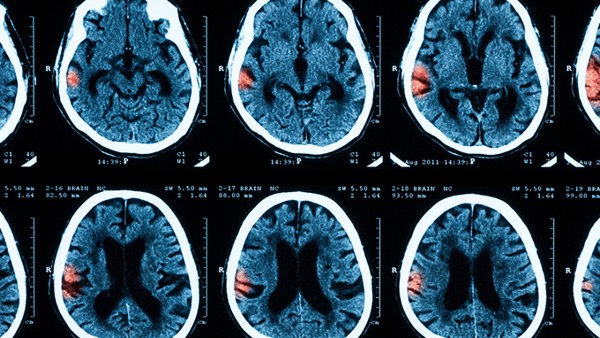

小脑延髓池又称后颅窝池,是蛛网膜下腔,在小脑干延髓之间形成的较大蛛网膜下腔间隙。这天然间隙主要位于小脑下和延髓后,小脑延髓池后为枕骨。通常情况下,一般健康的成年人,小脑延髓池宽约5mm,标准差约3mm。超过这个数值,小脑萎缩的可能性很高。小脑延髓池扩大,32周前胎儿比较常见。33周后开始缩小是比较常见的生理现象。

1、小脑延髓池是颅内正常蛛网膜下腔的间隙,是蛛网膜下腔局部宽度形成的脑池。小脑延髓池稍宽,临床上也是常见现象。

小脑延髓池增宽的原因

1、小脑延髓池增宽如果小于一厘米,有时只是胎儿发育过程中的生理现象,一旦宝宝脑中导水管系统发育成熟,消费能力恢复就会自然改善。

2、宽度在7厘米以上的话,有吸收障碍和脑导水管堵塞、胎儿子宫内感染、胎儿发育异常等可能性,需要积极复查。